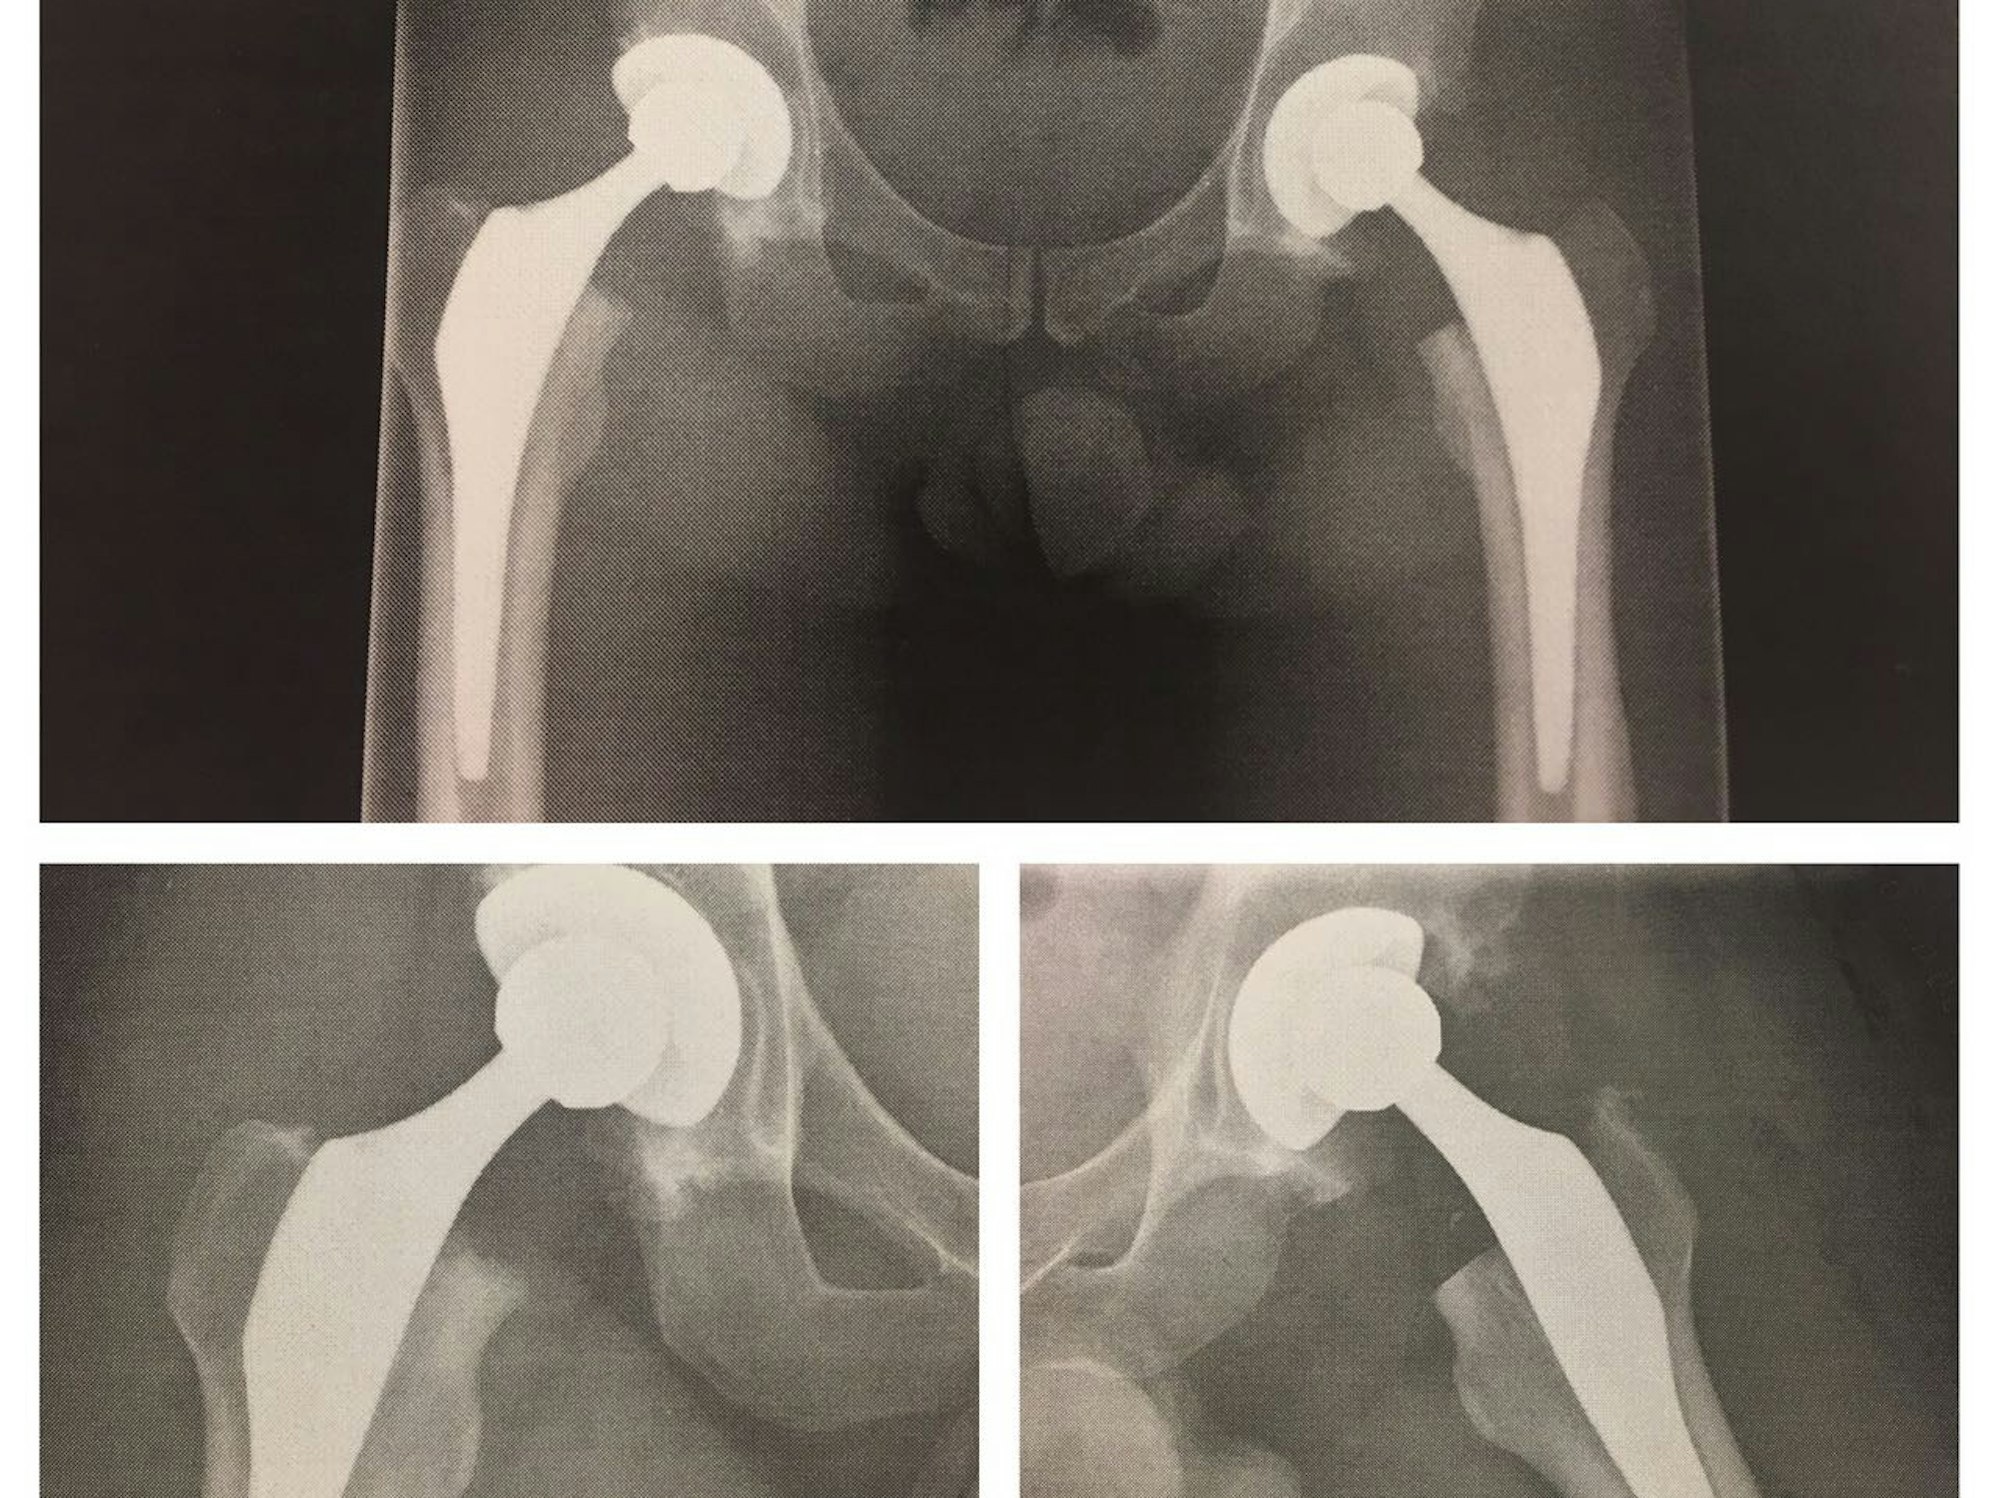

Die neuen Hüftgelenke sollen Charr zum Titel tragen.

Charr: „Ich bin so froh, dass Dr. Sieger und Dr. Tobolski in Köln das Problem gefunden haben, das mich all die Jahre belastet und mir Schmerzen bereitet hat. Die angeborene Dysplasie hat meine Hüft-Knorpel zerstört. Jetzt werde ich mich besser bewegen können als je zuvor und greife ich wieder an!“